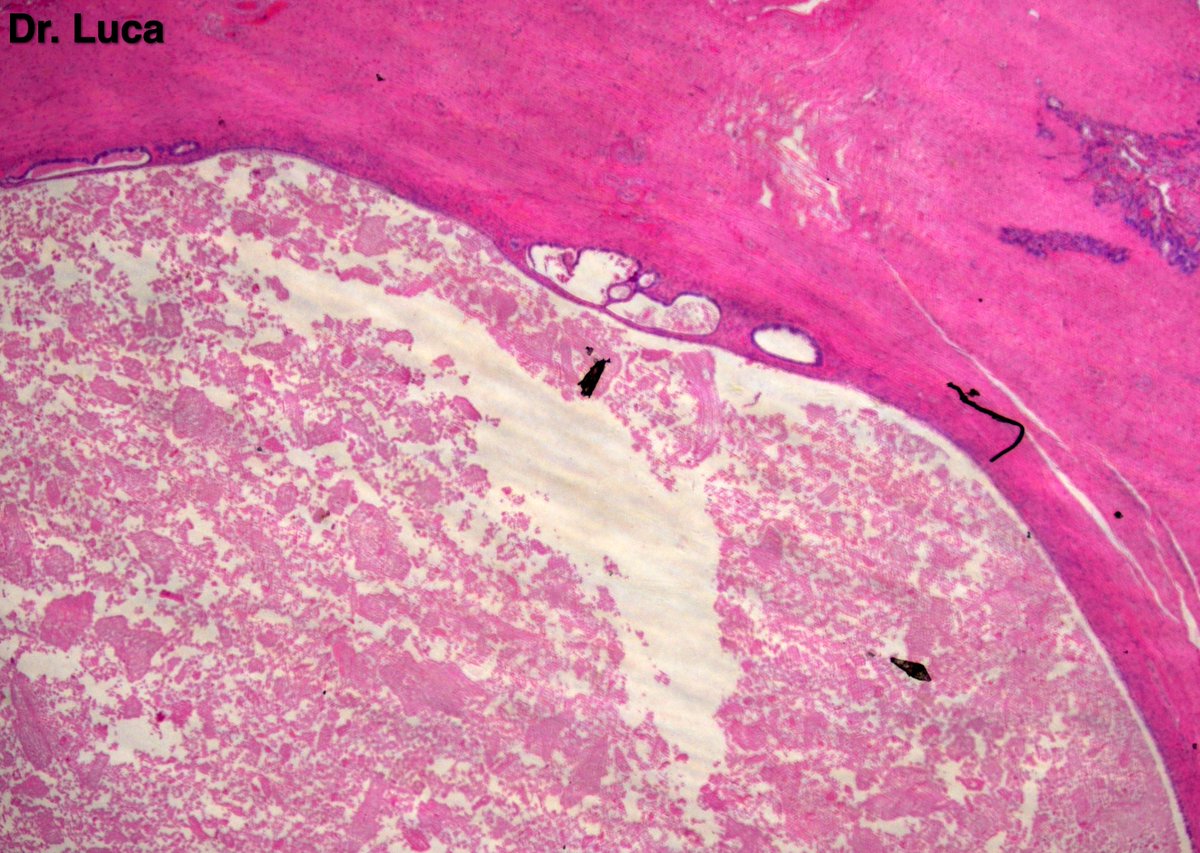

Kidney Monster! 3kg mass, 1% white solid areas, your Dx before H&E? @AkgulMd @Pathmath1 @goziemnweke @Teclis82 @MichelleDunno17 @PoloniaAntonio @kis_lorand @crazylymphocite @kriyer68 @D4L14H @ritaescarvalho @JPintoPath @Andres_Matoso @rajalbshah @Pathology36 #gupath #PathTwitter

10

19

48